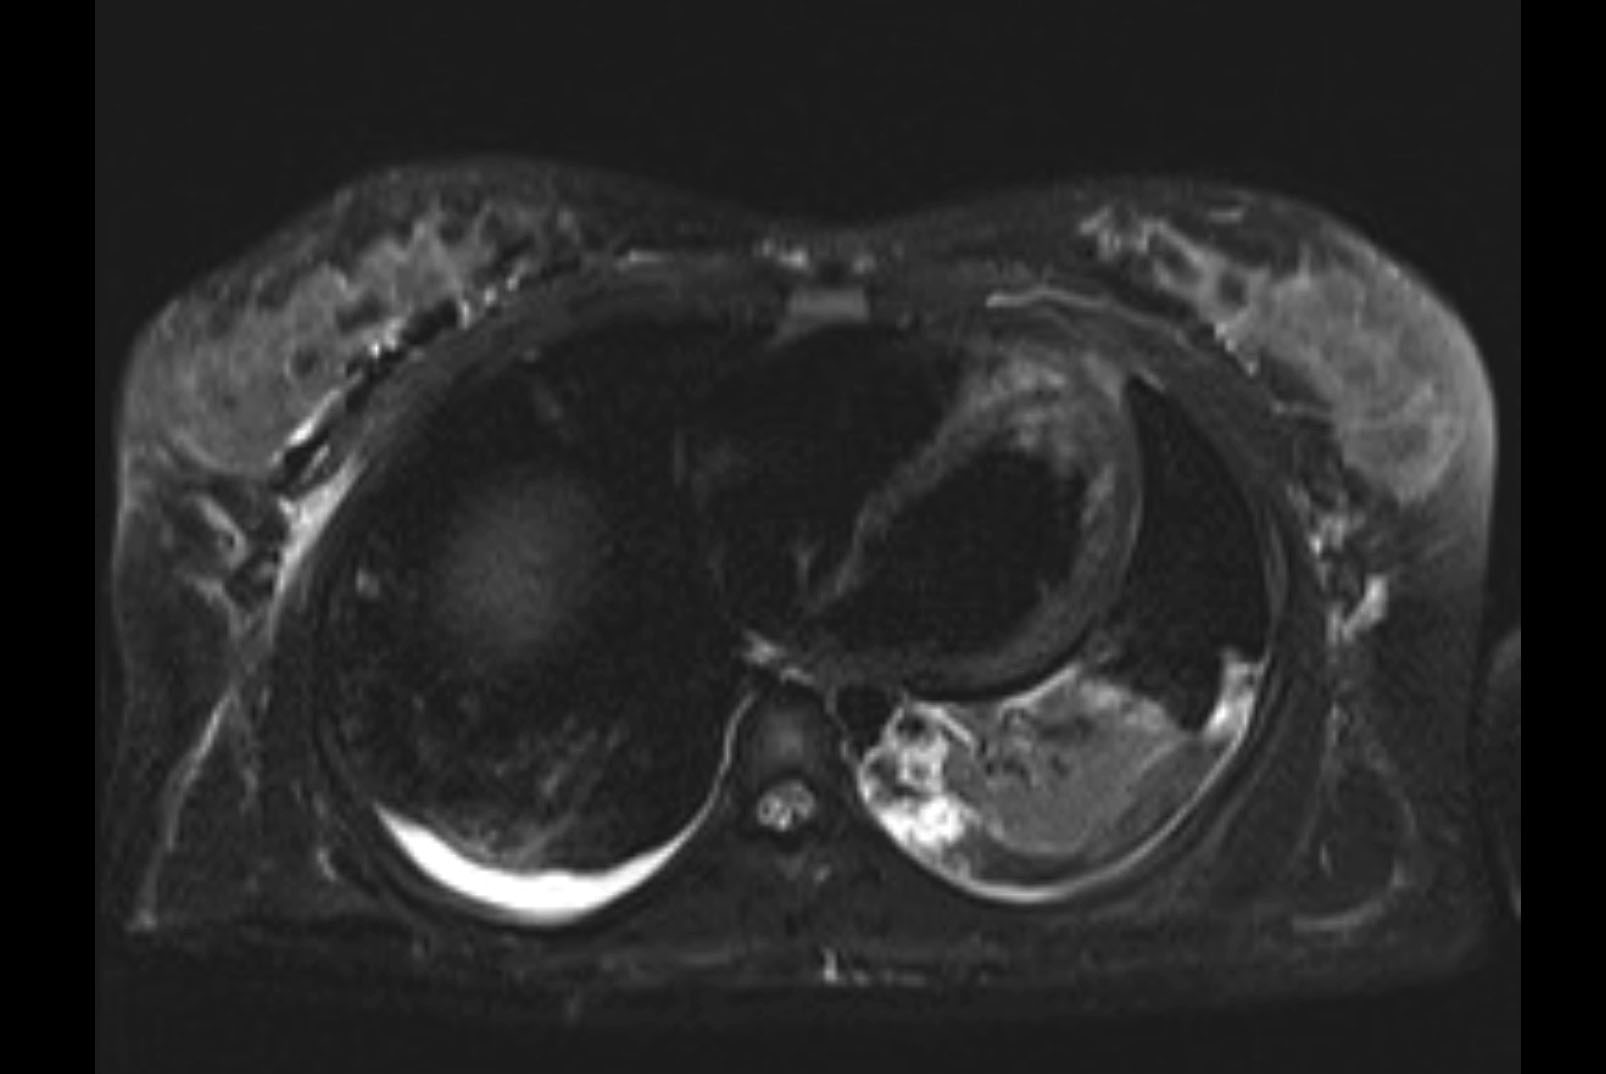

MRI T1

MRI T2

Imaging analysis

Based on initial findings, which issue(s) would you be most concerned about?